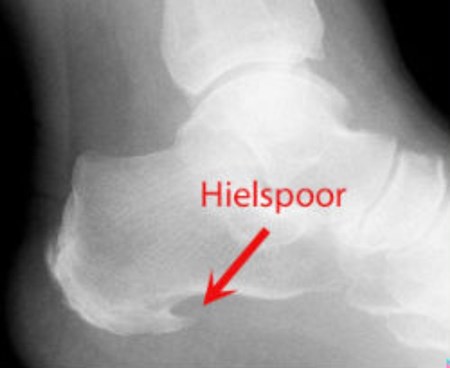

Wat is hielspoor?

In de volksmond wordt een fasciitis plantaris vaak een hielspoor genoemd. Een hielspoor is een beenvormig aangroeisel aan de onderzijde van het hielbeen. Dit aangroeisel komt ook heel vaak voor bij mensen die geen hielpijn hebben. Als er pijn is, wordt dit meestal door het peesblad veroorzaakt. Daarom hoeft een eventueel hielspoor niet met een operatie verwijderd te worden